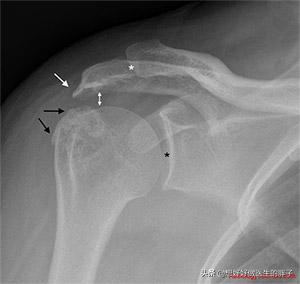

Schulterschmerzen aufgrund eines Impingement-Syndroms der Hüfte sind gekennzeichnet durchSchmerzen, die mit der Bewegung des Schultergelenks verbunden sind (zu unterscheiden von Schmerzen der Halswirbelsäule, die Schulterschmerzen verursachen)In einigen Fällen können die Schmerzen durch bestimmte Hebe- oder Abduktionsbewegungen der oberen Gliedmaßen ausgelöst werden, und bei einigen Patienten ist ein Klicken in der Schulter zu hören, wenn der Schmerz ausgelöst wird. In diesem Fall kann das Vorhandensein eines Problems oft durch eine Röntgenaufnahme oder eine MRT des Schultergelenks festgestellt werden.Wie Sie unten sehen können, ist der weiße Pfeil der Osteophyt des Akromions, der durch das Impingement entsteht, und der schwarze Pfeil stellt den Osteophyt des Tuberculum majus des Humerus dar, der auf das Akromion drückt.(ebd.).

Die Behandlung des Impingement-Syndroms der Schulter kann in Form vonbricht、Intraartikuläre Steroidinjektionen,Orale oder topische MedikamentezuRehabilitationsübungen zur Stärkung der SchulterBei einem Schulter-Impingement können die Muskeln um das Schultergelenk gestärkt werden, um die Erkrankung zu behandeln. Wenn die konservative Behandlung unwirksam ist und die Faktoren, die das Schulter-Impingement verursachen, nicht entfernt werden können, kann eine arthroskopische Schulteroperation erforderlich sein, um die Wucherungen zu entfernen.

(Das erste Bild unten zeigt die offensichtliche Bildung eines Knochensporns, das zweite ist ein postoperatives Bild nach der Operation zur Entfernung des Knochensporns, der das Schulter-Impingement verursacht hat).